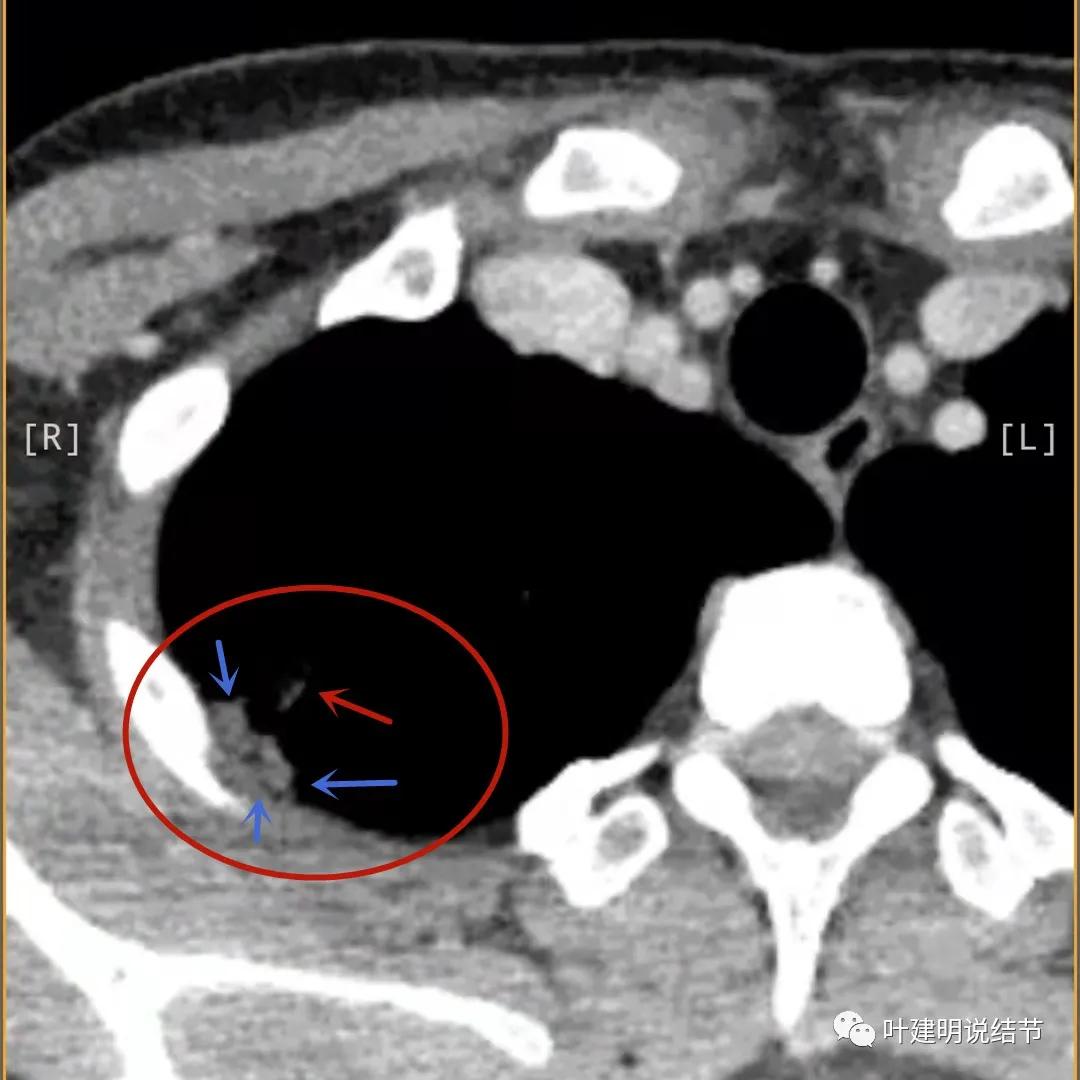

纵隔窗无钙化

蓝色箭头所指处居然有低密度影,难道是坏死?因为比肌肉密度低,也无强化,况且主病灶的中间也有个低密度的小点状

病灶有明显强化(说明炎性可能性大,如果恶性这样强化,血供丰富,应该倍增速度更快。蓝色箭头示胸膜处低于软组织密度的区域;桔色箭头示病灶边缘平直缺乏膨胀性;黄色箭头示中间的空腔

邻近胸膜处的增厚密度低于肌肉组织,病灶强化明显且均匀

此层也见明显的低密度区域(天蓝色箭头)

胸膜处明显增厚伴低密度区域

天蓝色箭头示病灶低密度区,考虑坏死可能性大,桔色箭头示边缘凹陷无膨胀性

上图示空洞偏心,而且红色箭头所指处与空腔似乎是整合,而非囊壁生长增厚。天蓝色箭头示近胸膜处的低密度区域,考虑坏死成分,囊壁的邻近部分也是极低密度区域,也可能是干酪样坏死区